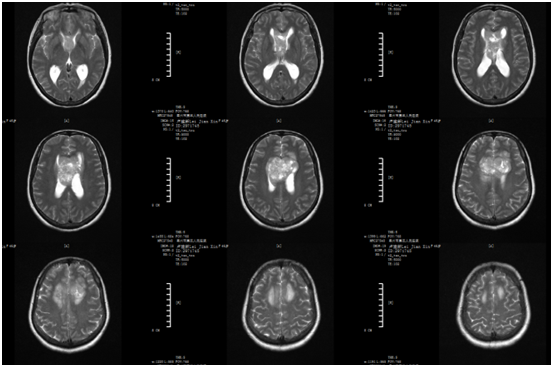

圖片來源 | 神外一區(qū) & 網(wǎng)絡(luò)